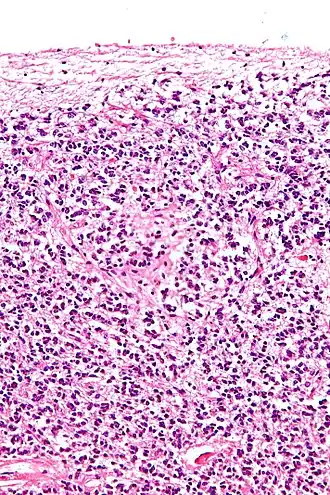

Поперечный разрез шишковидной железы, на котором видны пинеалоциты и другие клетки. |

Пинеалоциты — это основные клетки, содержащиеся в шишковидной железе, расположенной за третьим желудочком и между двумя полушариями головного мозга. Основной функцией пинеалоцитов является секреция гормона мелатонина, важного в регуляции циркадных ритмов(сна). У людей супрахиазматическое ядро гипоталамуса передает пинеалоцитам сигнал темноты и, как следствие, контролирует дневной и ночной цикл[1]. Было высказано предположение, что пинеалоциты происходят из фоторецепторных клеток[2]. Исследования также показали снижение количества пинеалоцитов путем апоптоза с увеличением возраста организма[3]. Существует два разных типа пинеалоцитов, тип I и тип II, которые были классифицированы на основе определенных свойств, включая форму, наличие или отсутствие складчатости ядерной оболочки и состав цитоплазмы.